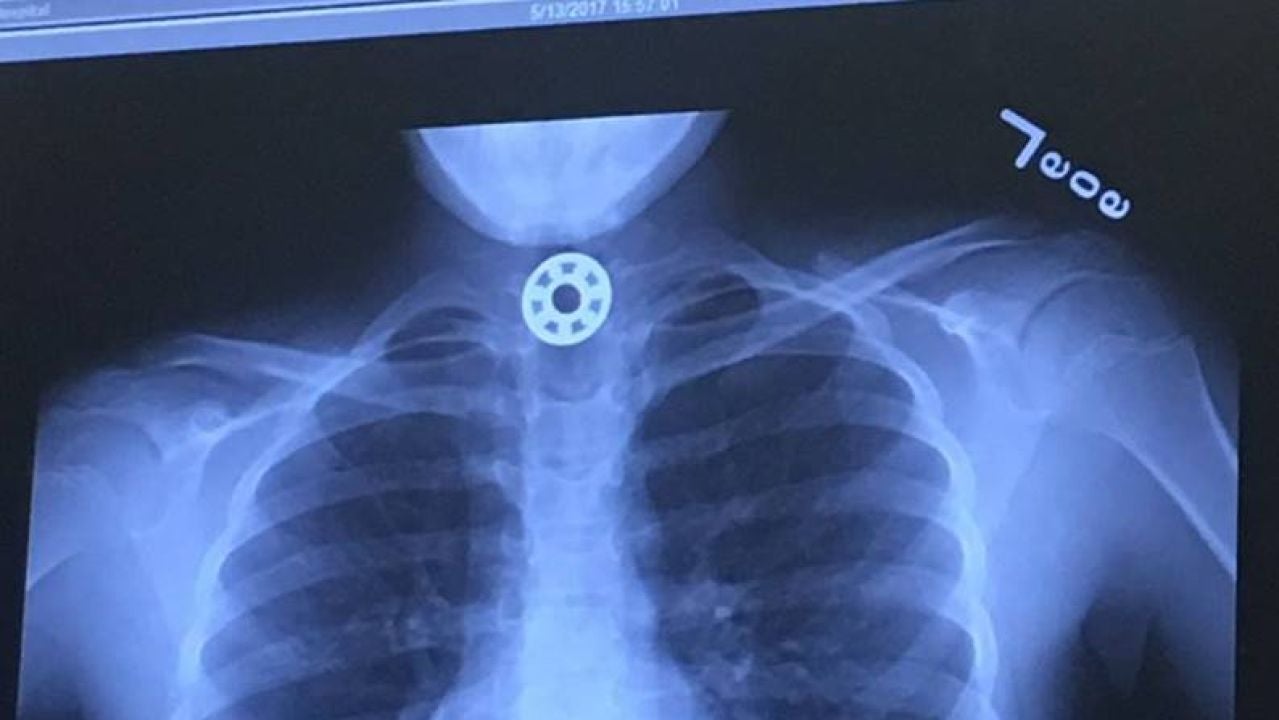

Radiografía de la niña que muestra el Fidget SpinnerFacebook

La madre, angustiada, trató de recibir ayuda médica rápidamente, pero los doctores no eran capaces de identificar dónde estaba el extraño objeto que la niña se había tragado. La pequeña fue trasladada al Hospital Infantil de Texas para que le realizaran una radiografía que mostró el juguete alojado en su esófago.